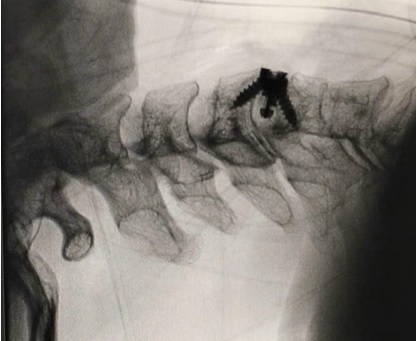

Hình ảnh chụp C-arm cột sống cổ sau phẫu thuật ACDF tầng C4–C5

Ca phẫu thuật diễn ra an toàn, thuận lợi. Dưới hỗ trợ của hệ thống C-arm trong mổ, kính vi phẫu phóng đại, ê-kíp kiểm tra chính xác vị trí phẫu thuật và dụng cụ cố định. Sau mổ, người bệnh hồi phục tốt: sau 5 ngày, triệu chứng đau cổ và tê bì hai tay giảm rõ rệt, chức năng vận động cải thiện, người bệnh được xuất viện trong tình trạng ổn định.